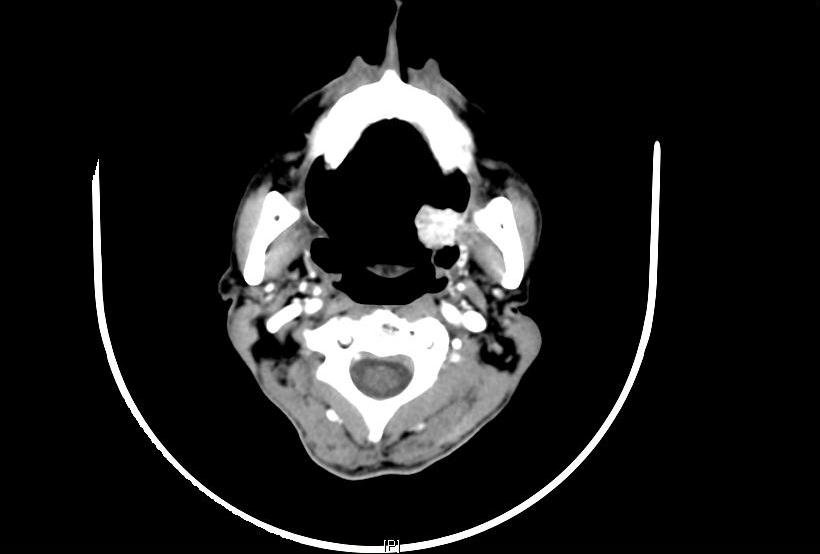

A 67 year male patient reported to Head and Neck Surgery OPD on February 2013 with history of a swelling on the left side of the oral cavity for the past one year. The swelling was insidious in onset, progressively increasing. He had no pain or no difficulty in opening the mouth. He had no history of neck swellings, voice change and respiratory difficulty. He had well differentiated squamous cell carcinoma of the tongue, T2N0M0 for which he underwent wide excision of left lateral tongue with primary closure followed by post-operative radiation of 50 Gy in 15 fractions at November 1994 in our institute. He was on regular followup and detected this swelling presently. He was disease free for a period of 18 years. Patient had no other significant medical illness or other relevant family history. On examination his general condition was fair, moderately built and nourished. Local examination revealed a large 4 x 4cm exophytic, reddish irregular polypoidal mass in the left retromolartrigone (RMT) region with areas of ulceration [Table/Fig-1]. On palpation, mass was firm, non-tender,pedunculated in the left retromolartrigone region. There was no other significant lesion in the oral cavity; initial operated site was normal with no significant induration. No regional lymphadenopathy was noted. Computed tomography (CT) [Table/Fig-2] scan of the lesion showed a large pedunculated lesion of size 2.7x 2x 2.5 cm lesion in the oropharynx originating probably from the left palatoglossal fold, protruding into the left tonsillar fossa. Soft and hard palate was not involved. The lesion is abutting the tip of the medial pterygoid muscle. Punch biopsy from the lesion showed tissue lined by hyperplastic squamous epithelium with sub-epithelium demonstrating infiltrating neoplasm composed of pleomorphic cells [Table/Fig-3] with moderate to abundant cytoplasm, round, irregular pleomorphic nuclei with nucleoli. Multinucleate tumor cells present. Cytokeratin [Table/Fig-4], EMA, HMB45 were negative, whereas Vimentin (mesenchymal tissue marker) [Table/Fig-5] and S-100 protein(nerve fiber) were strongly positive. With a history of pre-existing squamous cell carcinoma and radiation therapy and strongly positive vimentin, diagnosis of sarcoma is made. Treatment option of radical surgery with reconstruction was explained to the patient. As the patient wanted to be on follow up, he is being followed up regularly.

CT picture showing a large irregular heterogeneously enhancing mass lesion measuring approximately 27 x 20 x 25 mm is seen in the region of the left oropharynx. The lesion has a few foci of calcification within and a small stalk of origin, arising possibly from the palatoglossus fold protruding inferiorly into the left tonsillar fossa